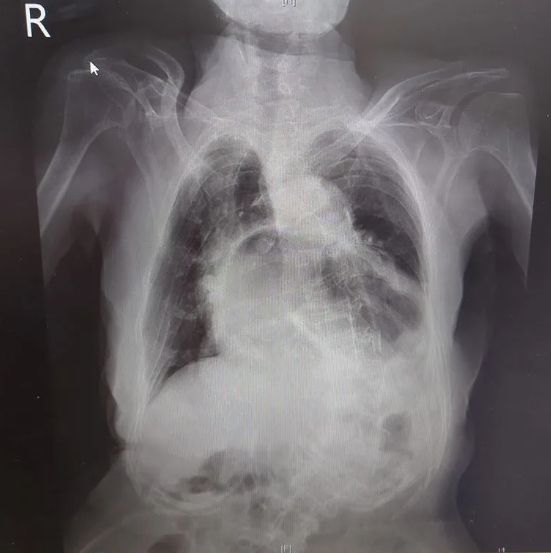

根據《ETtoday》報導,北市聯醫中興院區醫生姜冠宇透過社群平台曬出一張胸部X光片,無奈喊話:「這不是心臟,而是胃喔!」原來他早上遇到一名住在安養院的患者,因為她有胸悶、低血氧及嘔吐、食慾變差等症狀,趕緊安排就醫檢查,一照X光發現原本該是心臟的位置,竟變成了胃,甚至吃掉心臟,是典型的咳到胃翻出來的病例。

這病症確切病名為「胃疝脫」,主要是胃部錯位突破橫隔膜擠入胸腔,驚恐畫面讓人驚呼:「咳嗽太用力就會這樣嗎?」對此醫生也強調,一般咳嗽情況並不會這麼嚴重,而且也不是咳1、2次就能造成的,通常是長期咳嗽用力,可能是老一輩的人想把痰咳出卻沒有成功,只能不斷咳嗽藉此讓自己舒緩,咳久了之後橫隔膜的胃和食道接口也會越來越脆弱,這類症狀要多加留意是否有慢性呼吸道疾病,亦或是染疫後症候群導致!